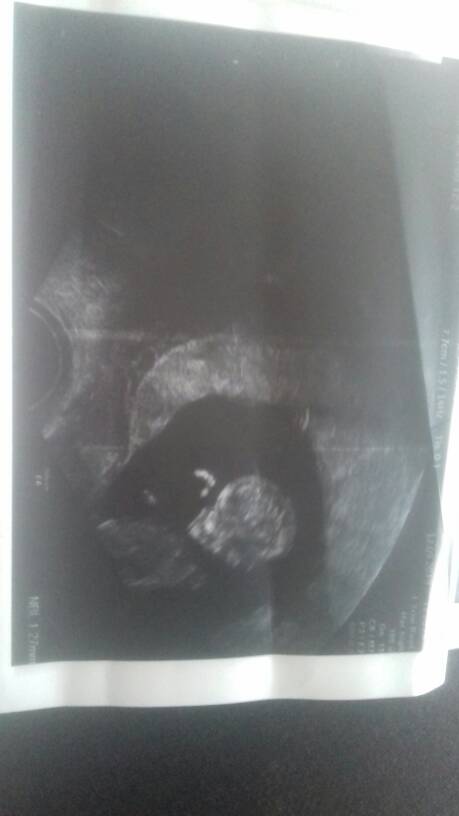

Maluszek ma 47cm 11t3d, serduszko bije 165bpm.

Przeziornosc karkowa 1.34 mm

Kość kosowa 1.27mm

Przeplywy wporzadku.

Nie zalecił żadbych dodatkowych badan gdyż ciąża rozwija sie prawidłowo[emoji5]Zobacz załącznik 1021645Zobacz załącznik 1021646Zobacz załącznik 1021647Zobacz załącznik 1021648